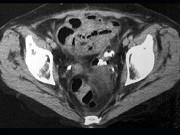

问题 女,54岁,直肠癌放疗后1月,阵发性腹痛腹胀,呕吐应,CT表现如图,应诊断为()

选项 A.小肠淋巴瘤 B.小肠结核 C.小肠Crohn病 D.放射性小肠炎 E.肠易激综合征

答案 D